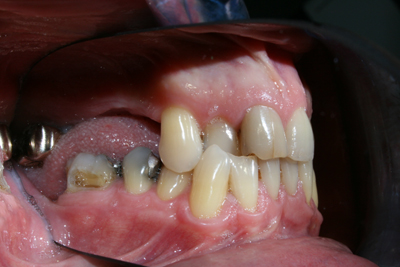

Caso ortodontico trattato con apparecchio Invisalign per riabilitazione preprotesica. Paziente di sesso maschile, età 42 anni, ha portato le mascherine nella fase attiva per un anno e successivamente preparato per impianti.

Paziente di sesso maschile, età 42 anni, ha portato le mascherine nella fase attiva per un anno e successivamente preparato per impianti.